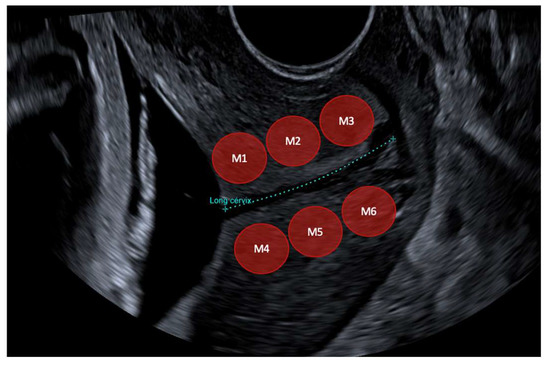

2.3. Cervical Shear Wave Elastography Measurement

| SWE M1 (Kpa) | 8.86 (6.63–9.98) | 10.46 (7.75–13.77) | 0.347 |

| SWE M2 (Kpa) | 7.94 (6.21–8.73) | 9.72 (7.37–12.35) | 0.062 |

| SWE M3 (Kpa) | 7.45 (5.87–8.61) | 8.31 (6.65–9.82) | 0.273 |

| SWE Mean anterior lip (Kpa) | 8.08 (6.34–8.87) | 9.49 (7.10–11.94) | 0.113 |

| SWE M4 (Kpa) | 9.13 (6.98–11.16) | 13.91 (10.0–17.900) | 0.023 |

| SWE M5 (Kpa) | 8.92 (6.71–10.88) | 10.60 (9.05–12.25) | 0.052 |

| SWE M6 (Kpa) | 8.15 (6.38–9.86) | 8.75 (7.57–9.95) | 0.288 |

| SWE Mean posterior lip (Kpa) | 8.73 (6.86–10.49) | 11.09 (9.05–13.76) | 0.022 |

| Mean SWE inner | 9.01 (7.41–10.58) | 12.18 (9.16–15.18) | 0.071 |

| Mean SWE outer | 7.81 (6.41–8.69) | 8.53 (7.83–9.30) | 0.090 |